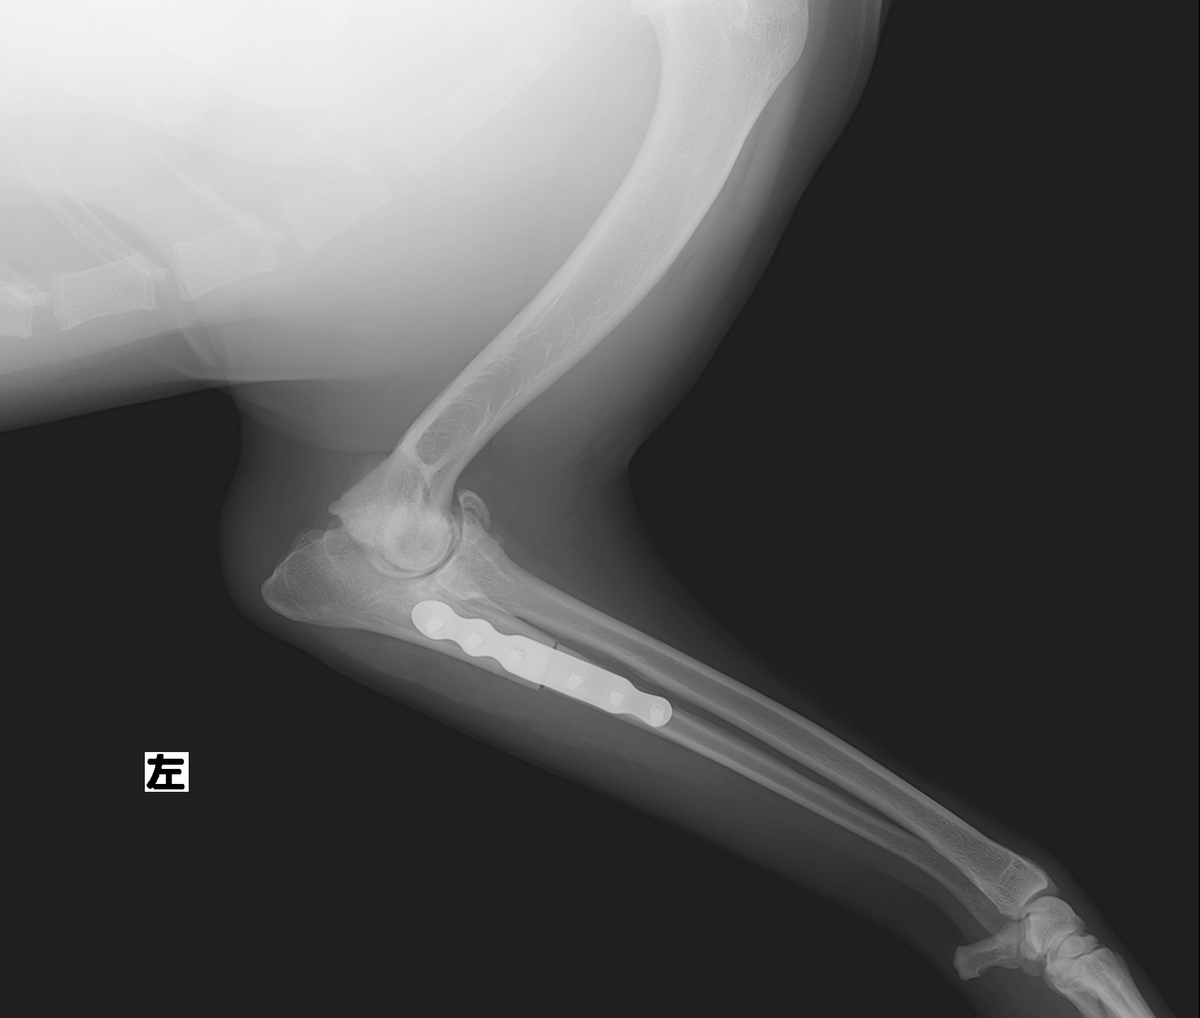

治療は、PAUL (近位尺骨外反骨切り術)という手術を実施しました。

この手術は、前腕の尺骨近部を骨を切って、角度を変える事により体重を内側から外側へ変化させる方法です。これにより、内側にかかる負担を軽減することができます。